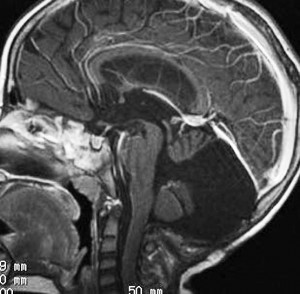

思春期の女の子にできた小脳腫瘍です。とても大きく見えますがほとんどが水たまり(のう胞といいます)。第4脳室が腫瘍で圧迫されて閉塞性水頭症になりました。のう胞の中に出血がありますが毛様細胞性星細胞腫では腫瘍内出血をしばしば見ます。右の写真で脳室が大きくなっています。こんなに大きいのに小脳症状は全くなくて,頭痛と嘔吐が症状でした。

赤で塗ったところだけが毛様細胞性星細胞腫です。これを取れば治ります。簡単な手術ですし後遺症も残りません。

手術後のMRIです。水頭症も改善してますから症状も消失しましたし,すぐに退院です o(^o^)o